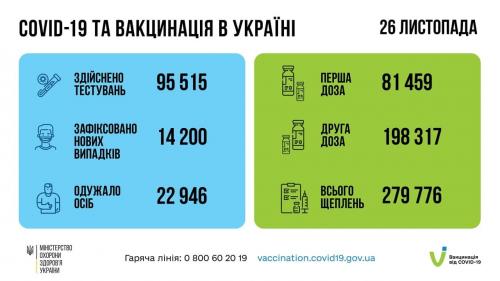

МОЗ: Уперше з початку пандемії було зроблено понад 100 тисяч ПЛР-досліджень за добу